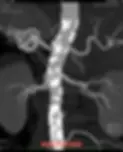

Ipertensione renovascolare aterosclerotica

Una condizione ad altissimo rischio

L’immagine mostra una angio-TAC di un’aorta addominale affetta da gravissima aterosclerosi. Le aree bianche sono placche aterosclerotiche calcificate. Quando queste placche ostruiscono le arterie renali ostacolano l’apporto di sangue al rene che, per cercare di mantenere la sua funzione di filtrazione comincia a produrre renina in quantità eccessiva e così facendo aumenta la pressione arteriosa.